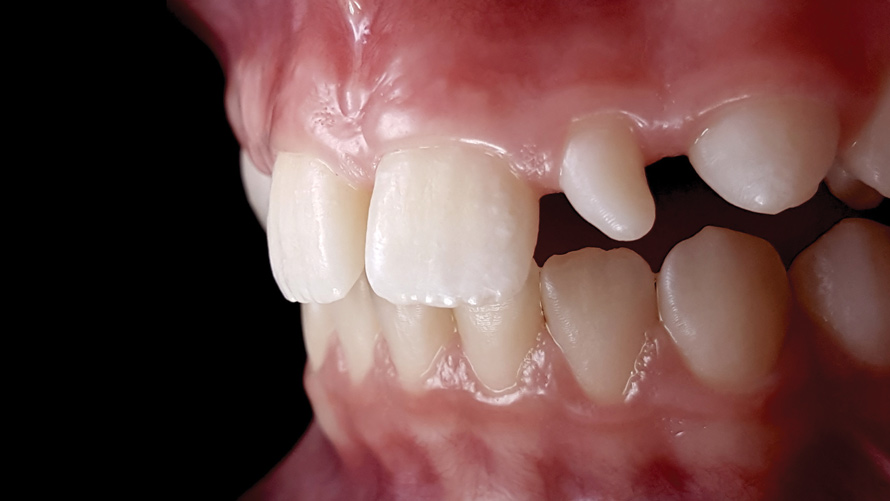

(12. and 13.) Intraoral photographs taken with a smartphone and an EALS device for orthodontic evaluation.

Figure 12

Figure 13

One of the main advantages that smartphone cameras have over DSLR cameras is that nearly everyone is already very familiar with the technology; therefore, the incorporation of these devices into everyday practice does not require learning a new and unfamiliar skill set. The task of producing a series of high-quality clinical photographs for routine examinations (Figure 8), esthetic treatment planning (Figure 9 through Figure 11), or specialty care (Figure 12 and Figure 13) can be delegated with confidence to any staff member during the patient's initial office visit and will generally require less than 5 minutes of time to complete. When a DSLR camera is used, evaluation of the intraoral images either takes place on the small viewfinder built into the camera or necessitates the physical removal of the memory card from the camera to downloaded the images onto a computer for review. An added bonus of smartphone dental photography is that the phone's screen now replaces the much smaller viewfinder of a DSLR camera and provides the clinician with the ability to view and zoom into the patient images on a 5- to 6-inch, high-definition display.